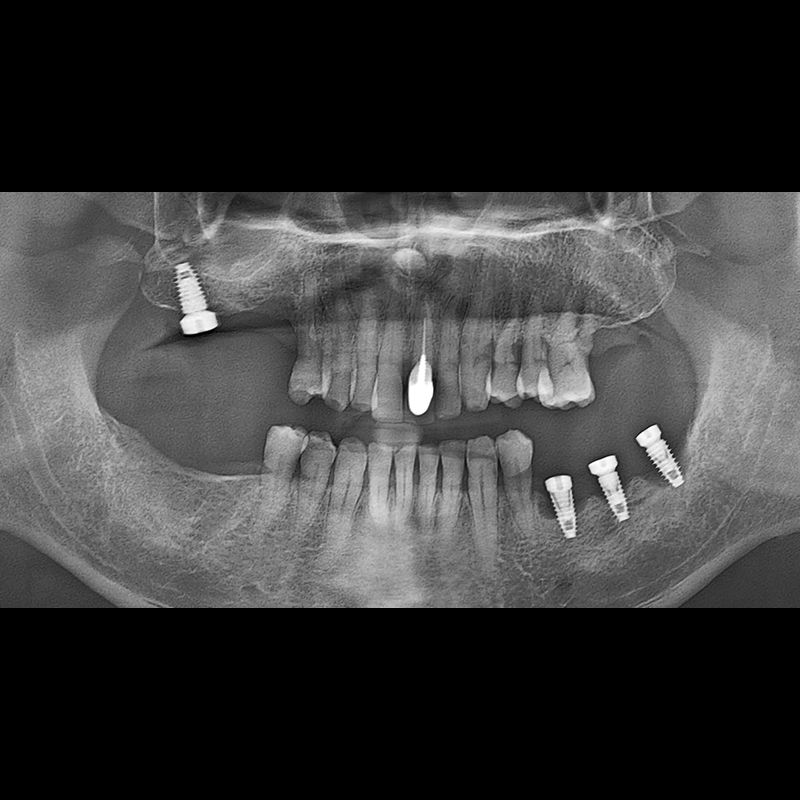

BEFORE AFTER

임플란트 전후사진 2025.05.30

결손된 치아 부분과 살리기 힘든 치아 위치에 임플란트를 식립하였습니다.